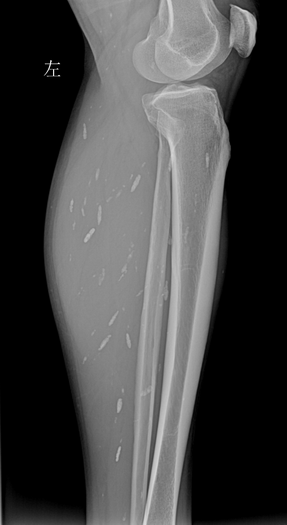

左小腿X光片,见肌肉内多发囊虫病灶。